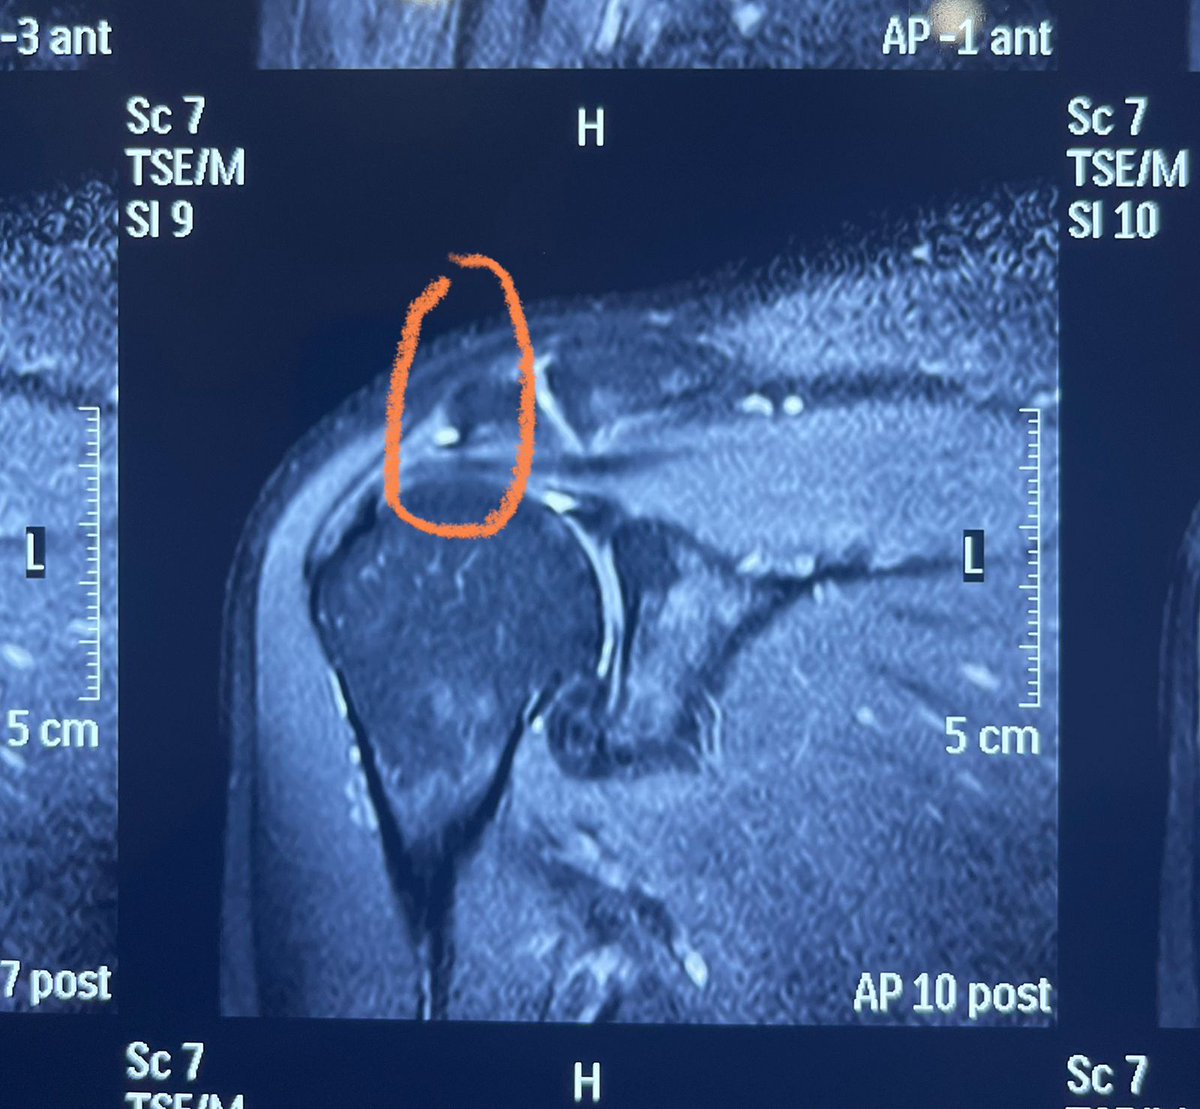

Konda Vishweshwar Reddy

Konda Vishweshwar Reddy@KVishReddy·

Had a knee meniscus tear 6 months ago. Neglected it, the tear got bigger. Had a Minimal invasive knee surgery last night. In the hospital till Monday. Could not postpone it further. Will be back in action in two weeks.

Konda Vishweshwar Reddy tweet mediaKonda Vishweshwar Reddy tweet mediaKonda Vishweshwar Reddy tweet media